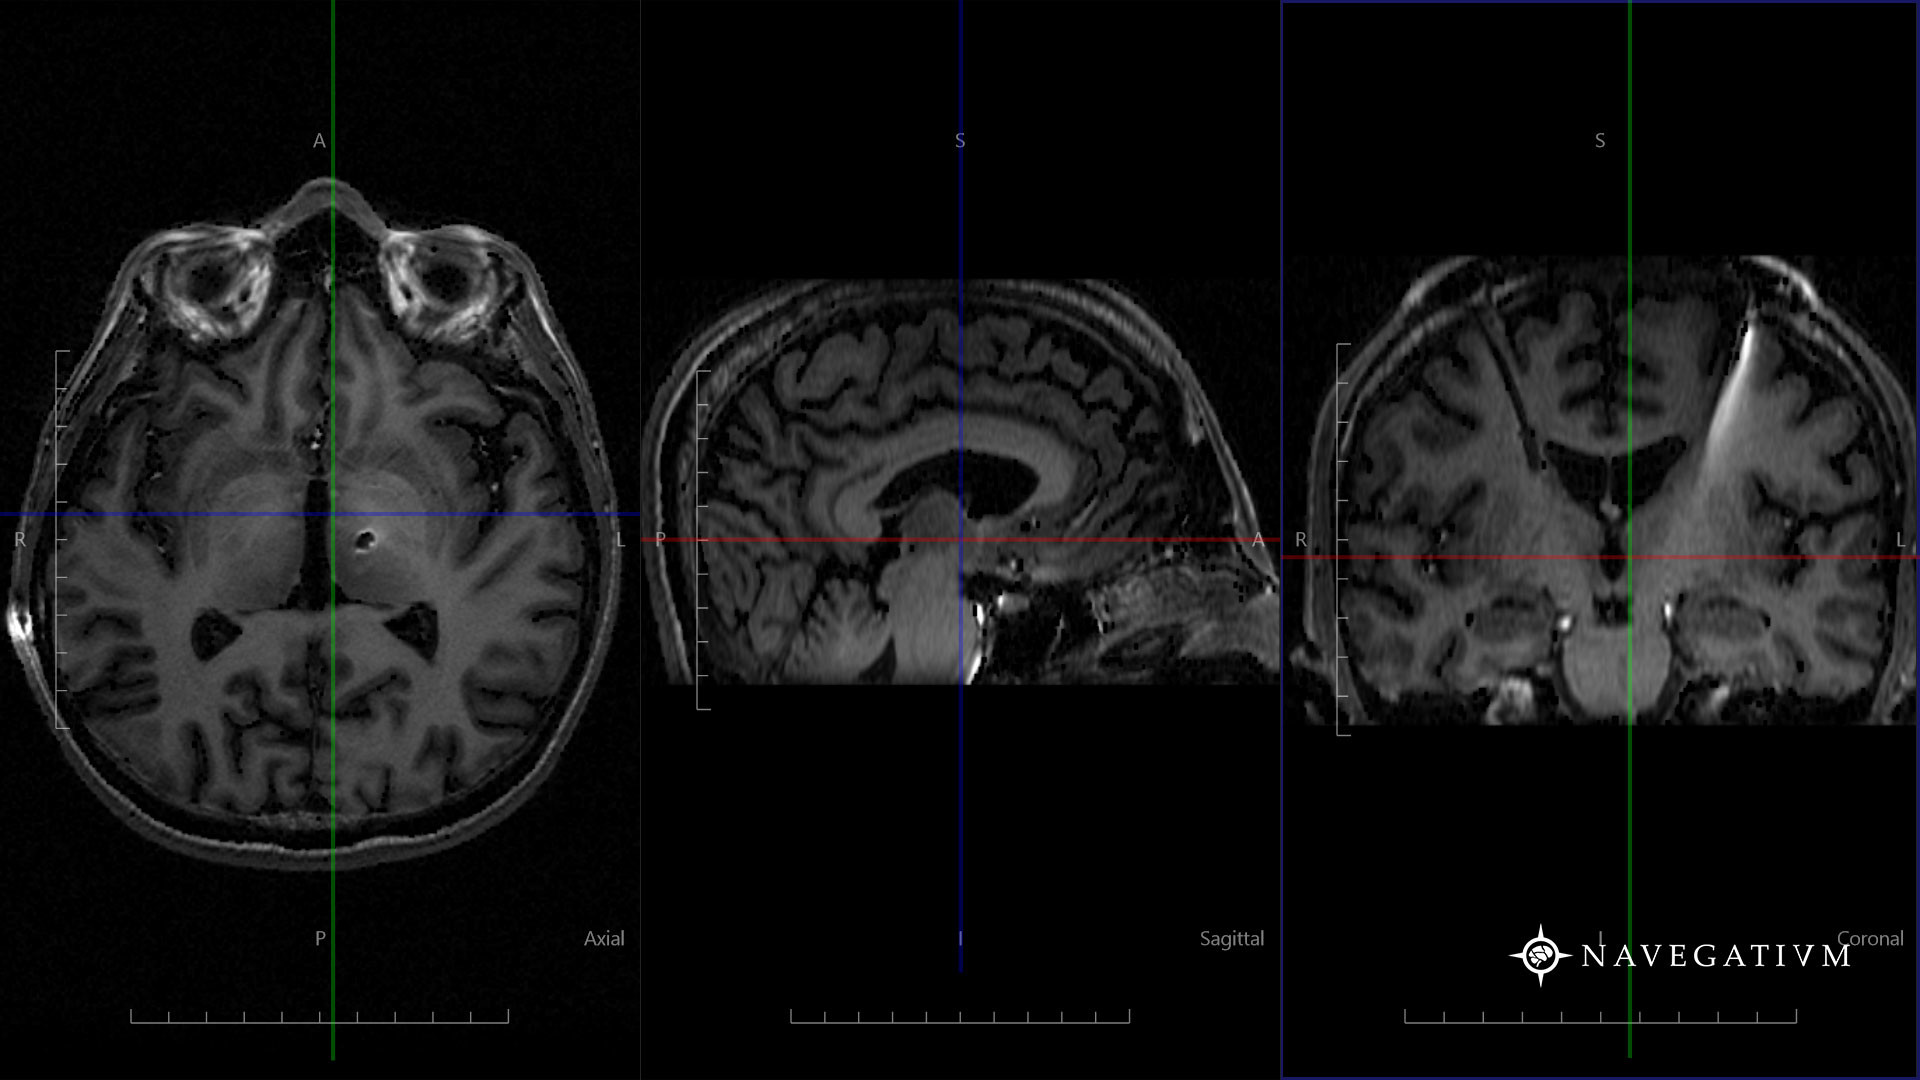

Closeup Of A Ct Scan With Brain And Skull On It Stock Photo 107572736

Source: shutterstock.com

scan ct brain skull closeup shutterstock footage vectors illustrations.